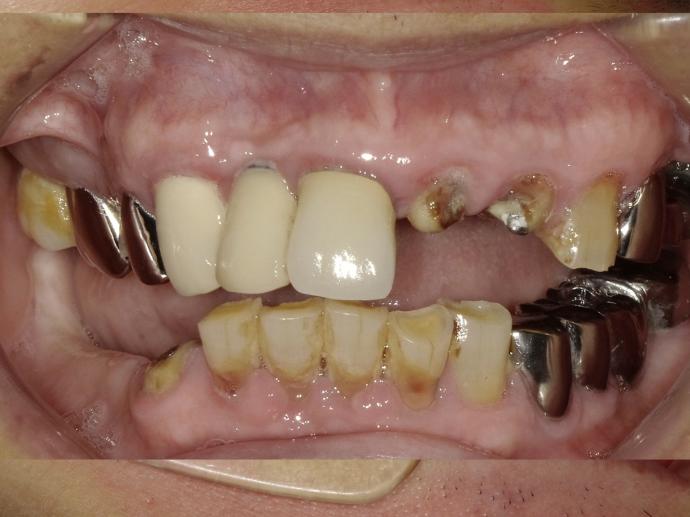

術前 / 術後

年屆八十的曾先生住竹山,為人幽默風趣。之前長年佩戴的活動假牙總覺得不甚方便。曾先生說,「老蒙老,還要哺土豆」,希望能夠用植牙取代活動假牙。一面不必再拿上拿下清洗,一面能咬較硬的食物,充分享受美食帶來的樂趣。

曾先生血壓較高,但在安馨溫馨的手術室中,以醫療級血壓血氧儀全程監控,將血壓監控在安全的範圍內。幾次手術下來,完成八顆的植牙,也達成他能享受美食的心願。